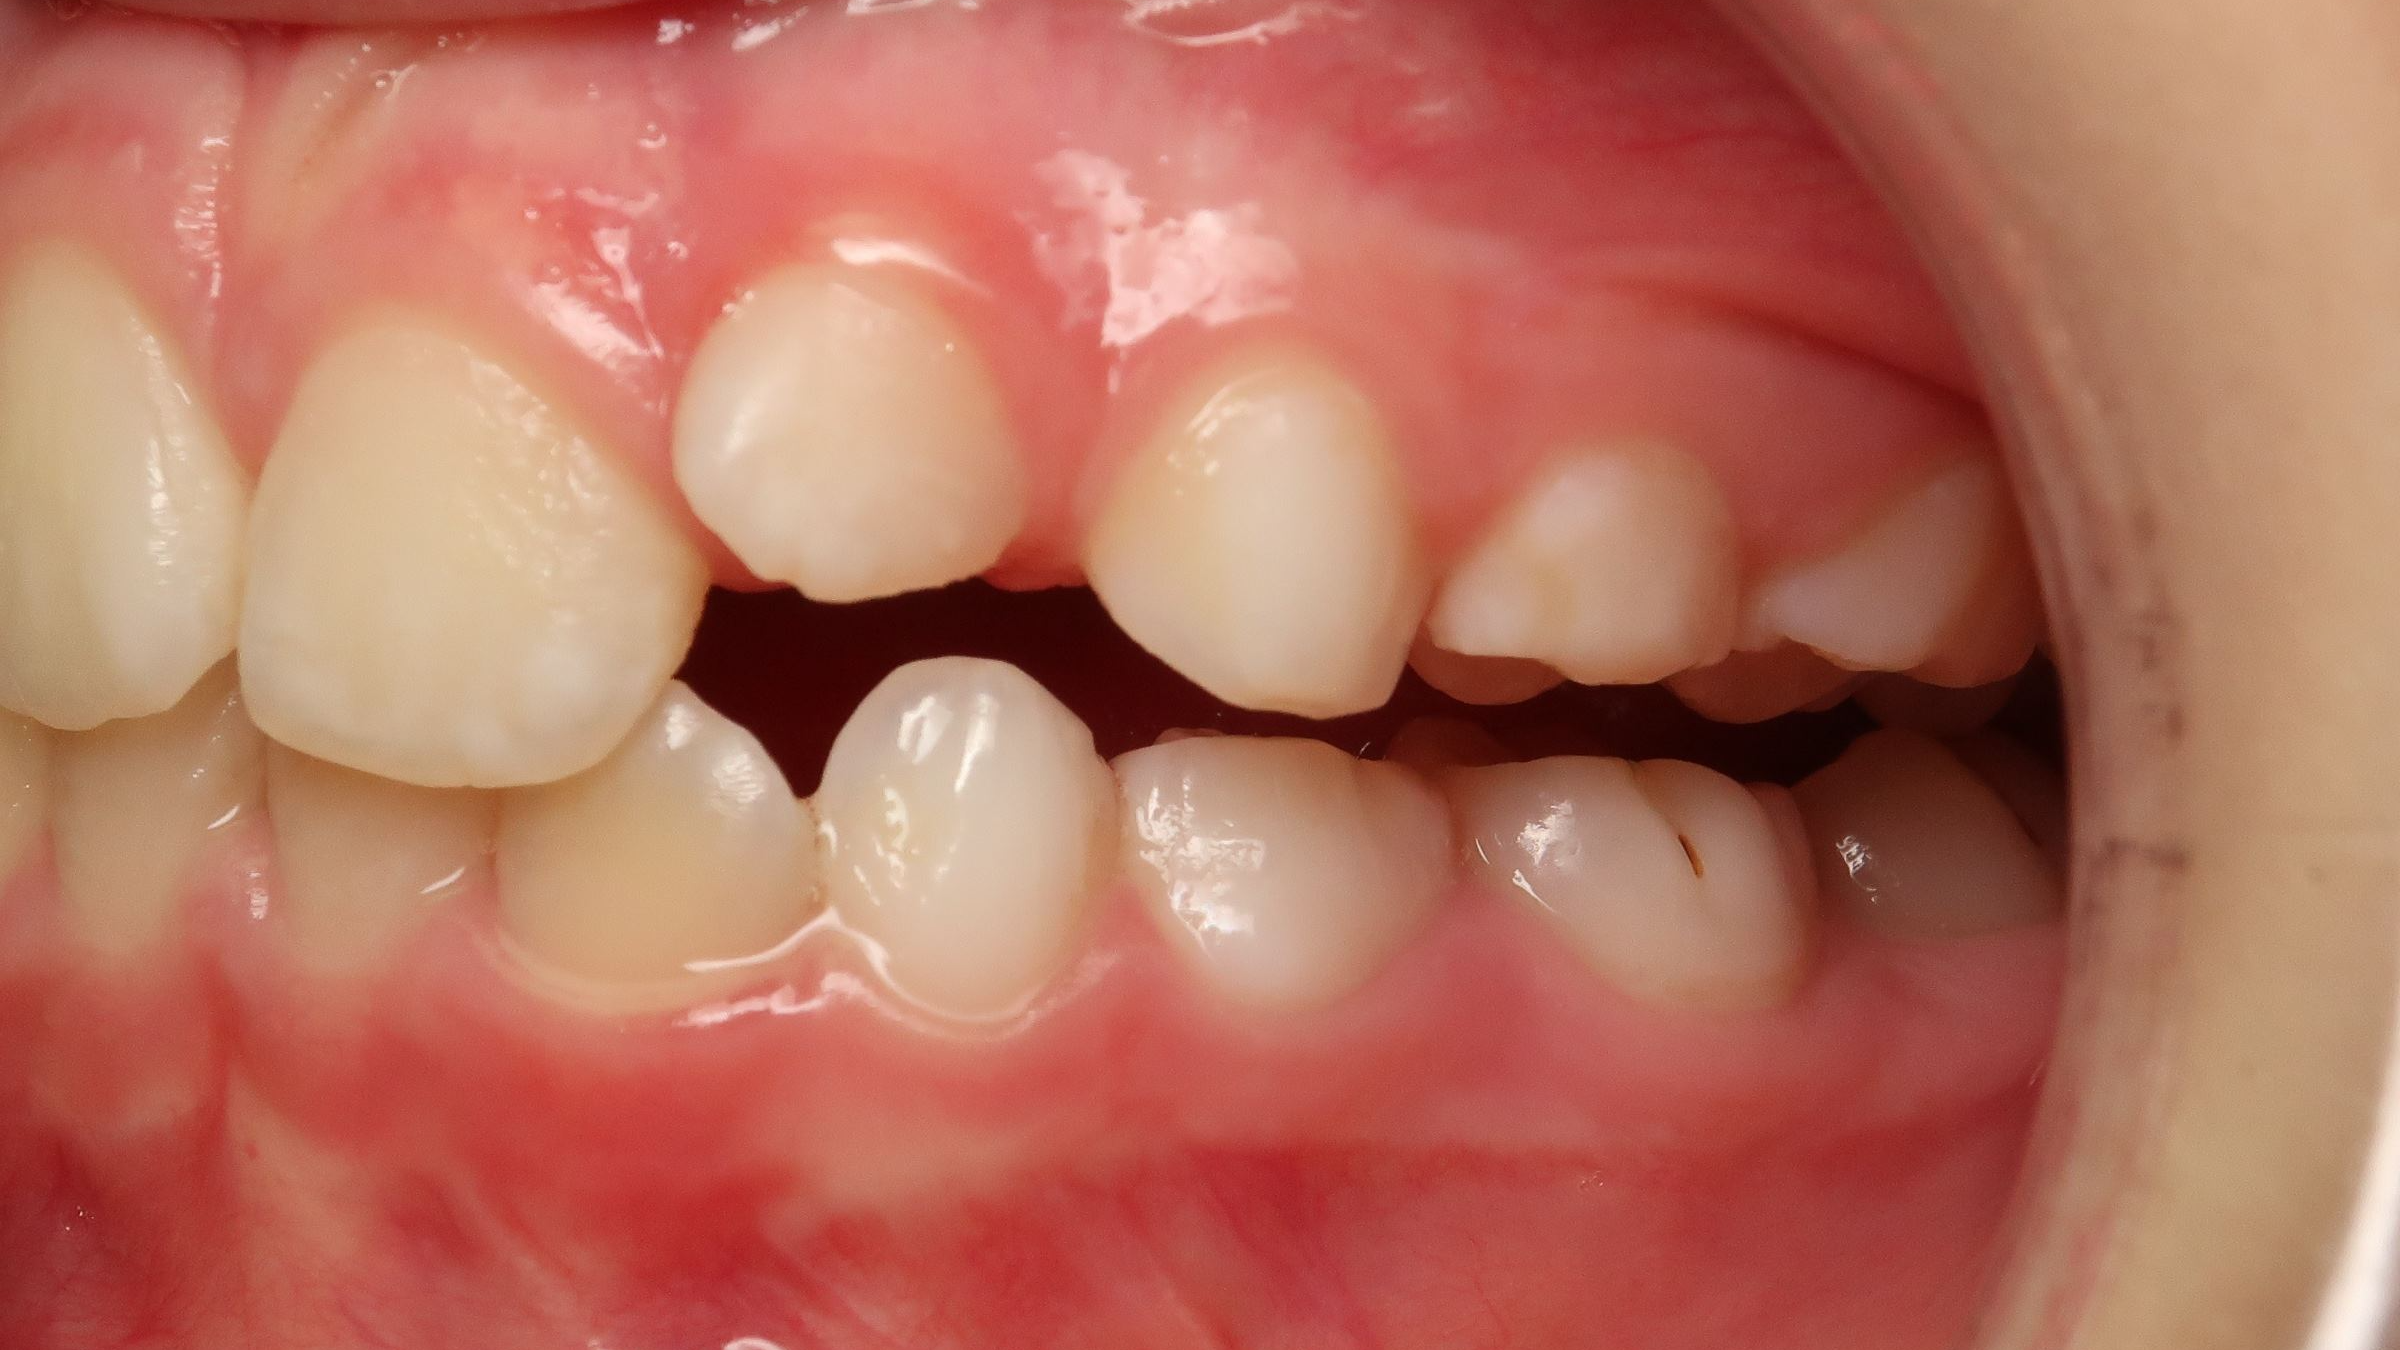

inversion des dents postérieur coté droit